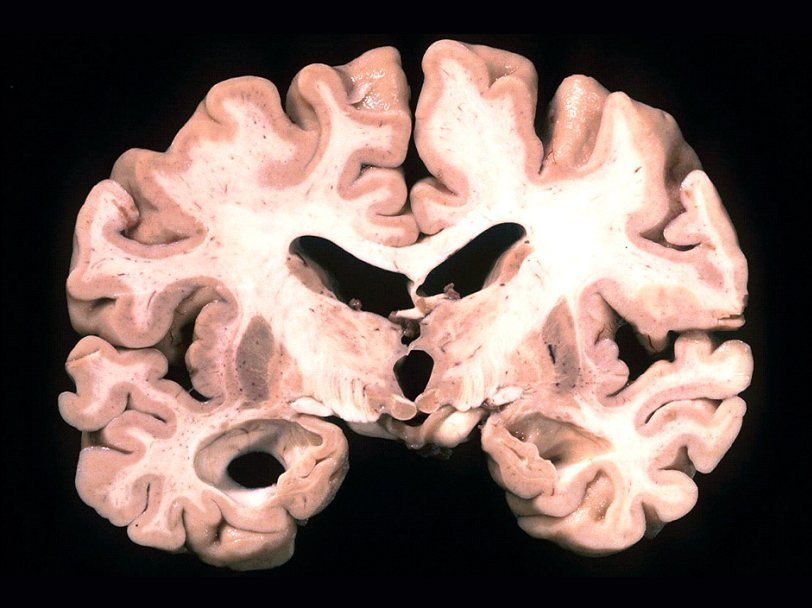

Следы присутствия грибов отмечены и в самих нервных клетках, и в пространствах между ними. Больше всего свидетельств присутствия грибов обнаружили в лобных долях, а также в мозжечке и гиппокампе. Все эти структуры страдают на последних стадиях заболевания, а в гиппокампе патологические изменения появляются одними из первых. Помимо этого, грибы нашли в сосудистом сплетении мозга. Это может объяснить, почему у пациентов с болезнью Альцгеймера часто есть нарушения работы сосудов мозга.